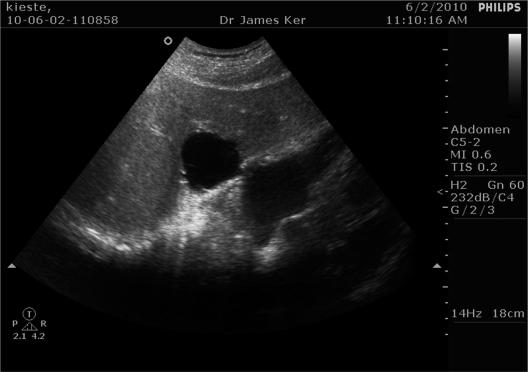

肝脏与右心房 - 肝囊肿作为心律失常的一个病因。

The liver and right atrium-hepatic cyst as a cause of arrhythmia.

Simple hepatic cysts are a relatively common radiological finding. These cysts may be classified as parasitic and non-parasitic. They are usually asymptomatic, but may cause symptoms due to local compression. These compressive complications include: portal hypertension, edema due to caval compression, extrinsic gastric compression and duodenal compression with obstruction.However, no reports in the literature exist describing atrial compression by hepatic cysts.In this case report a simple hepatic cyst causing slight right atrial compression is described. This slight compression is the cause of atrial premature beats.It is proposed that simple hepatic cysts may be the cause of atrial premature beats.

单纯性肝囊肿是一种相对常见的影像学表现。这些囊肿可分为寄生虫性和非寄生虫性。它们通常无症状,但可能因局部压迫而引起症状。这些压迫性并发症包括:门静脉高压、腔静脉压迫导致的水肿、外在性胃压迫和十二指肠压迫伴梗阻。然而,文献中尚无关于肝囊肿压迫心房的报道。在本病例报告中,描述了一例引起右心房轻度压迫的单纯性肝囊肿。这种轻度压迫是房性早搏的原因。有人提出单纯性肝囊肿可能是房性早搏的病因。